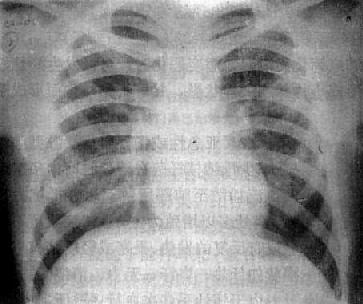

(1)结核球:结核球(tuberculoma)为纤维组织包绕干酪样结核病变而成。系因空洞引流支气管阻塞,空洞被干酪样物质充填所致。可呈圆、椭圆及分叶状。多为直径2~3cm的单发球形病变,也可多发。多见于锁骨下区,但可发生于任何部位。一般密度均匀,轮廓光滑,但中心可有小空洞存在。结核球内可以出现层状、环状或斑点状钙化影(图3-1-25)。结核球附近常有散在纤维增殖性病灶,常称为卫星灶。

右肺结核球

图3-1-25 右肺结核球

右肺内带可见椭圆形致密影,轮廓光滑,内有斑状钙化